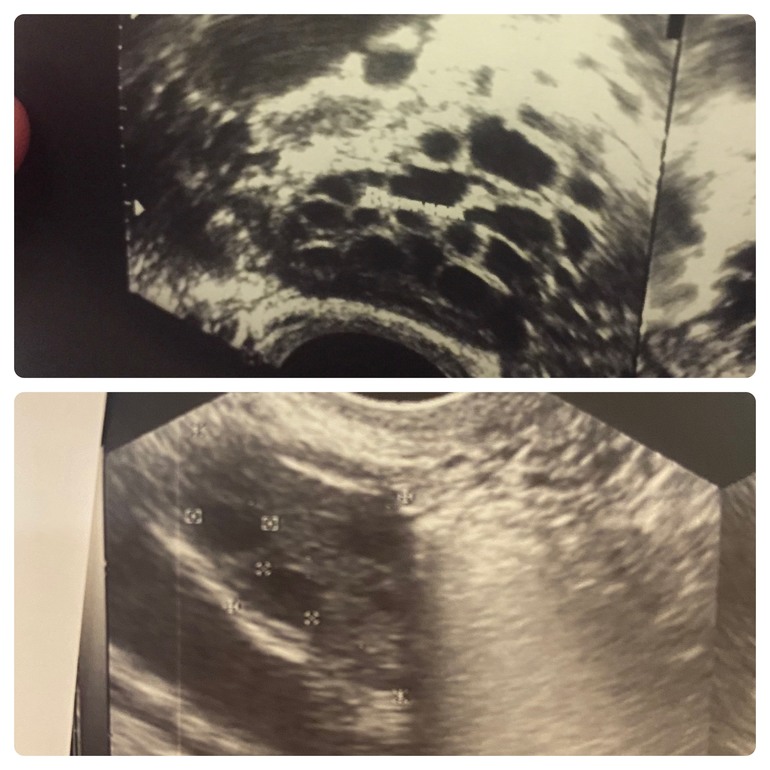

Да, СПКЯ и гиперандрогения. Вот разница у меня по узи, сверху типичное состояние яичников из цикла в цикл, снизу позавчера на фолликулометрии

Спасибо, всего месяц по 2000, но дальше также продолжаю принимать, честно говоря, в бесконечной борьбе с СПКЯ особо не верила в результат, поэтому не поверила на узи, что это мои яичники.